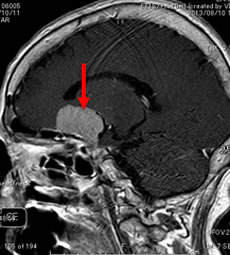

当院での症例をお示しします。症例は66才女性、進行する左眼の視力(左:手動弁)、視野障害にて当院来院。MRIにて赤矢印のように左蝶形骨内側に大きな腫瘍を認めます。開頭手術治療前に腫瘍の栄養血管にカテーテルを入れて、固体塞栓物質を造影剤と混ぜて注入します。最後に再開通しない様プラチナコイルを留置して終了します。その2日後に腫瘍摘出を行いましたが、出血は少量で輸血も行っておりません。視力も左は1.5まで改善し、患者さんは元気で退院しました。(図1-a・b、図2-a・b、図3-a・b、図4-a・b)

図1-a:術前 |

図2-a:術前 |